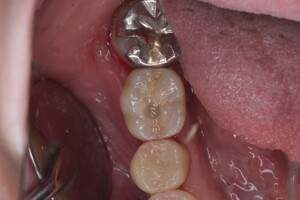

症例写真-1

- Befor

- After

症例写真-2

- 途中経過

| 年齢 | 50代・男性 |

|---|---|

| 主訴 | 右下歯が疼く |

| 治療内容 | ・右下6番インプラント ※1:FGG(遊離歯肉移植術)とは、足りない歯ぐきを上顎から上皮を切り取り移植する外科手術 |

| 治療費 | 合計:902,000円(税込) ■内訳 |

| 治療期間 | 9ヵ月 |

| 治療方針 | 右下の当該歯は歯根破折により保存不可能と診断しました。歯周疾患も伴っていたため抜歯後に骨吸収※1が大きく起こることが予測できました。チタンメッシュ併用骨再生誘導法(GBR※2)を選択しインプラント埋入と同時に行い自然な歯槽骨のラインを再現しました。またGBRを行う際にインプラント辺縁の付着歯肉の減少が起こる為、遊離歯肉移植術(FGG※3)を行い清掃性を考慮した形態に仕上げました。 ■治療方針の解説 治療した右下の歯をレントゲンで撮影したところ根本の部分に黒く写る箇所があり「根尖性慢性周囲炎※1」と診断。また歯周病も進行していました。 ※1 骨吸収・・・歯槽骨という歯を支える骨がなくなっていくこと |

| 担当者所見 | 主訴の右下だけでなく歯茎の腫れ、発赤があり不良補綴や不良充填など他にも治療箇所が多数ありました。プラークコントロールが不良であった為まずはブラッシング指導を行いセルフケアの重要性を理解していただくところからスタートしました。 右下6番の歯はインプラント治療を行なった結果審美的にも機能的にも患者様の満足を得ることができました。骨造成と歯肉移植も行なった為インプラントを支える十分な歯周組織の獲得ができたと思っております。 |